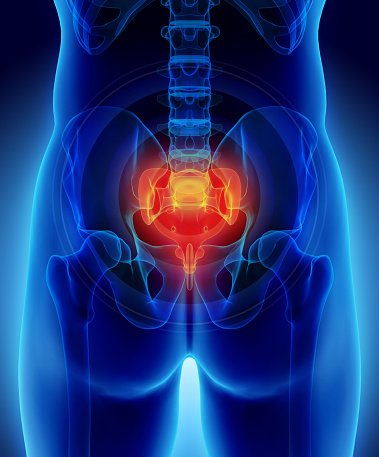

Localizado na região do cóccix, o problema é incômodo e doloroso

Também chamado de cisto sacrococcígeo, o cisto pilonidal é uma doença relativamente comum em adolescentes e adultos jovens, geralmente observada dos 15 aos 30 anos de idade, acometendo o sexo masculino em 80% dos casos. Trata-se de uma inflamação crônica, localizada na região do cóccix. É bastante incômoda e dolorosa por ser com tratamento cirúrgico.

O cisto pilonidal fica localizado no cóccix, região acima da prega glútea, e devido à proximidade com o ânus e também com a parte final da coluna vertebral muitas vezes causa dificuldade diagnóstica e os pacientes costumam percorrer diversos especialistas antes de terem o diagnóstico corretamente firmado.